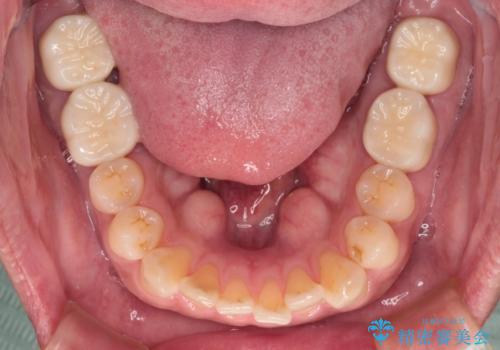

- 奥歯の間から出血するとのことで来院された患者様です。

口腔内は非常にきれいで、定期的に歯科医院でのクリーニングも行っているとのことでしたが、歯肉からの出血が一向に解決しない状態でした。

奥歯の歯間部の歯肉が炎症で赤黒くなっており、歯周ポケットを検査したところ、6-8mm(正常では3mm以下)であり、外科処置が適用となる状態でした。

まずは仮歯に置き換え、歯周ポケットを除去するための外科処置(歯肉弁根尖側移動術)を行い、治癒を待ってセラミッククラウンにて補綴治療を行うこととしました。